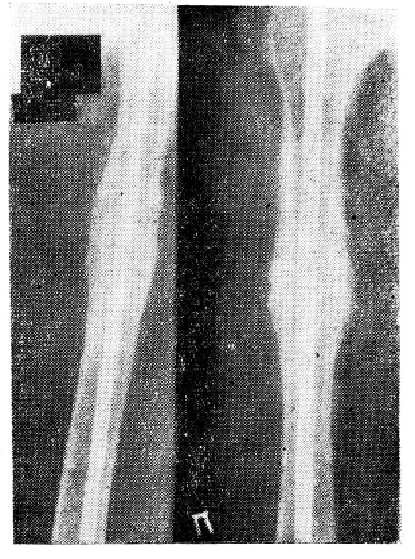

Так, больной А., 25 лет, 29/Ѵ-59 г. получил открытый оскольчатый перелом. В течение 6 месяцев находился в гипсовой повязке, но перелом не сросся. При подступлении диагностирован несросшийся оскольчатый перелом правой большеберцовой кости вследствие нарушения консолидации (рис. 1). 15/ХІ-59 г. произведена операция создания нового очага костной регенерации. Из здоровой большеберцовой кости выпилен трансплантат, который подсажен в подкожную клетчатку брюшной стенки. На больную конечность наложена новая циркулярная гипсовая повязка. Через 2 месяца после операции (14/1-60 г.) патологической подвижности нет. На рентгенограмме видна хорошая консолидация перелома (рис. 2).

Рис.1 Несросшийся оскольчатый перелом большеберцовой кости у больного А. вследствие нарушения консолидации. 6 месяцев после травмы. Консолидации перелома нет.

Рис.2 Через два месяца после операции создания нового очага костной регенерации на другой голени у больного А. Операции на месте перелома не производилось. Видна хорошая консолидация перелома.